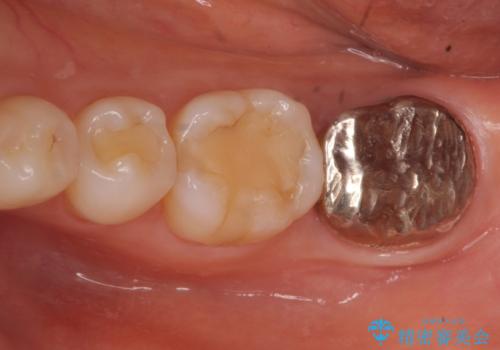

- 昔何回か根管治療した奥歯が膿んでいていて痛みがあることを主訴に来院された患者様です。

精査したところ、左下の奥歯にはひびが入っていて、保存不可能な状態でした。

義歯・インプラント・親知らずの移植の選択肢を提案したところ、移植をご希望されました。

割れている奥歯を抜去後左上の機能していない親知らずを移植し、生着したのち根管治療・補綴を行いました。